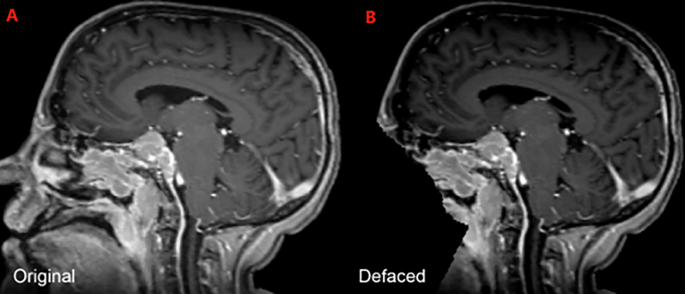

Following anonymized DICOM-RT data collection from each respective institution, the raw DICOM-RT data were converted to Neuroimaging Informatics Technology Initiative (NIfTI) format using open-source software30. This process ensured that each MRI scan was accurately captured in its native spatial orientation and voxel resolution without any intensity resampling. To preserve extracranial anatomy and anatomical structures relevant to RT (e.g., stereotactic headframes, fixation devices), no skull-stripping was applied22,23,24. Instead, patient facial features were removed using the Analysis of Functional NeuroImages (AFNI) automated defacing algorithm with AFNI’s default parameters26,27,28. The AFNI defacing process eliminates patient-identifiable facial structures while retaining the rest of the cranial and extracranial volume as shown in Figs. 2C, 5.

Example of a sagittal image of a brain MRI from the BraTS-MEN-RT training set, both before (A) and after (B) automated defacing.